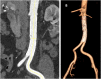

Case report: A 56-year-old female with no risk factors for vascular disease but with history of a mild COVID-19 infection in the previous month, for which she had started anticoagulant therapy at a prophylactic dosage, developed an acute ischemia of the lower limbs and was diagnosed with floating thrombosis of the abdominal aorta. The thrombus was excluded from the aortic blood flow by deployment of a stent-graft in the abdominal aorta. At 12 months, the patient was well, and the thrombus in the abdominal aorta appears to be completely excluded by the stent-graft. A review of the available literature from 1980 to 2022 showed 74 cases of AFT located in the aortic arch, in the descending thoracic and in the abdominal aorta. In most cases the AFT involved the aortic arch (38/74, 51.3%) and/or the descending thoracic aorta (30/74, 40.5%), while the abdominal aorta was involved in 6 cases. In 2 of these 6 cases, the patients had a COVID-19 infection. The AFT was mostly approached either medically with anticoagulation/systemic thrombolysis (32/74, 43.2%) or with surgical removal (31/74, 41.9%), while endovascular coverage of the thrombus with an endograft was performed in 6 cases of AFT located in the aortic arch and in the descending thoracic aorta (3 cases each).

Conclusion: There is no consensus about the optimal treatment of AFT. In selected cases, abdominal stent-grafts may be used for stabilization and exclusion of symptomatic abdominal aorta floating thrombosis to prevent progression and recurrent embolization.